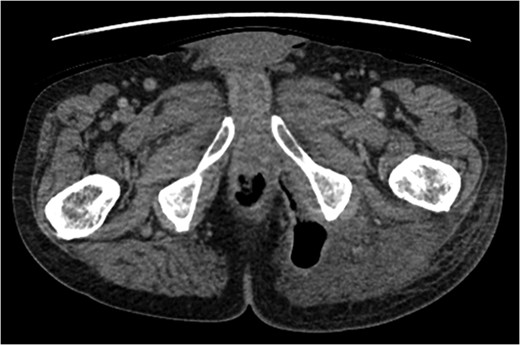

A rare complication of diverticular disease is the formation of fistulas, most commonly either colo-vesical or colo-vaginal. We present the unusual case of a perforated sigmoid diverticulum forming a colo-gluteal fistula and presenting initially as a gluteal abscess in an otherwise asymptomatic patient. After drainage of the gluteal abscess, the patient re-presented with faecal loss from the abscess drainage site. Imaging revealed fistulous communication between the sigmoid and the left obturator internus muscle, tracking to the gluteus maximus with associated abscess and cutaneous communication to the site of previous drainage. The patient underwent an emergency Hartmann's procedure with lay open/abscess drainage of the gluteal cavity. Post-operatively the patient experienced continuing discharge from the gluteal fistula despite repeated drainage and debridement causing considerable morbidity, inconvenience and misery. Clinicians should maintain a high index of suspicion when presented with a gluteal abscess and should consider the possibility of an intra-abdominal source.

An emergency Hartmann's procedure was performed under general anaesthetic through a lower midline incision as well as lay open of the perineal fistula. On opening the abdomen, a perforated diverticulum was identified extending into the left lateral pelvic wall. A standard Hartmann's procedure was performed, with sigmoid colectomy, division of rectum at recto-sigmoid junction and a tension-free stoma formed in left hypochondrium. The left buttock abscess cavity extended by a further 2–3 in. and the cavity then packed.

Following the operation, the patient had a short and uncomplicated critical care stay and was subsequently discharged. He has since continued to experience ongoing discharge from the fistula with follow-up imaging showing a reduction in the size of the abscess cavity but continuing patency of the fistula tract, despite repeated wound debridement and packing, drainage of the fistula and rectal washout.